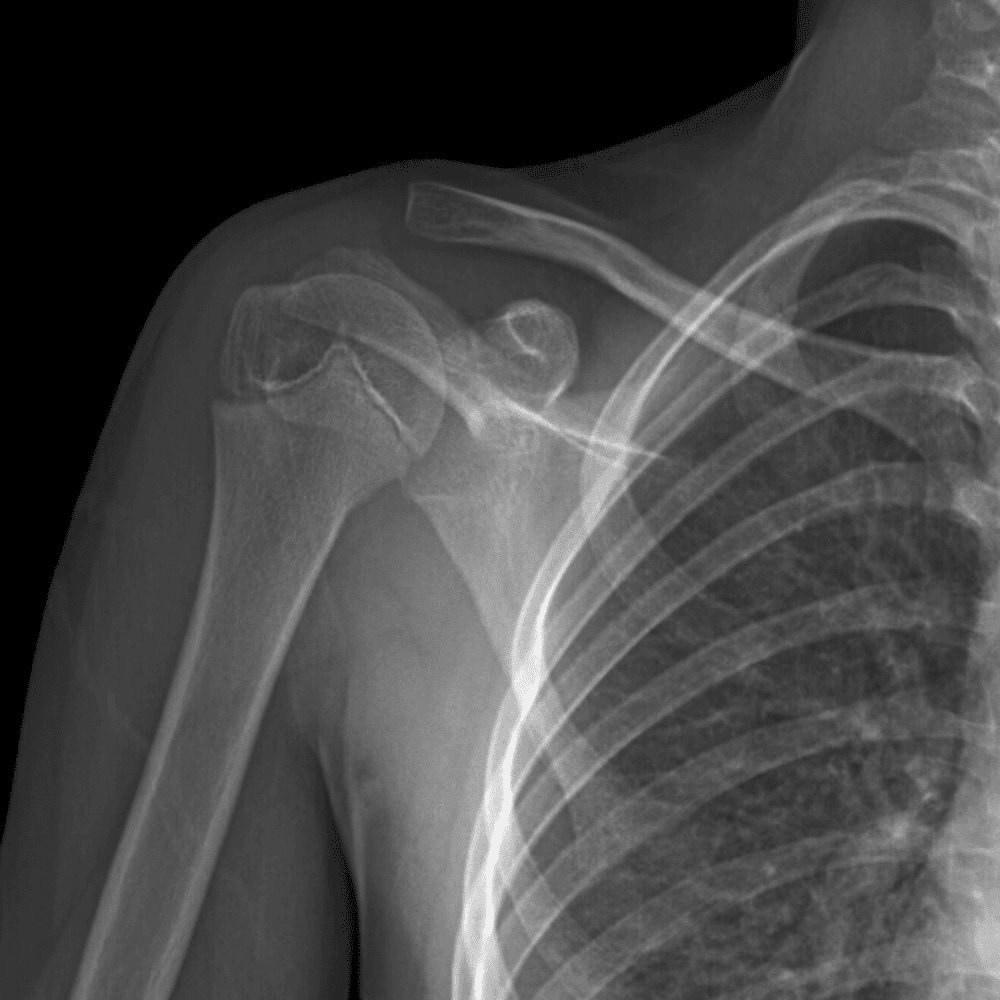

Simuliert den Dienst durch subtile oder schwierige Fälle und einige Normalbefunde.

30 Fälle